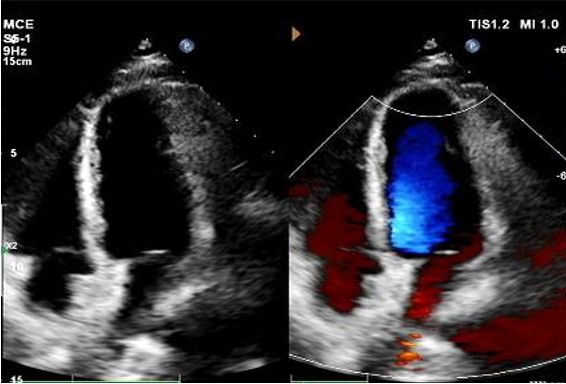

Diagnosis: Positive bubble study.

No residual shunt observed.

Gradual reduction in device echogenicity.

1-Year Echo:

No visible disc structures – replaced by 8mm tissue thickening at the septal implant site.

Zero residual shunt (rest or post-Valsalva).

Complete device absorption confirmed.